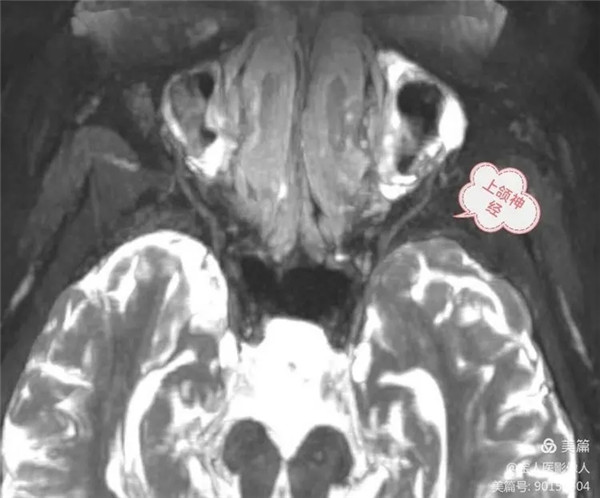

三叉神經顱外段第二分支-上頜神經

上頜神經自三叉神經節發出后,立即進入海綿竇外側壁,之后經圓孔出顱,進入翼腭窩,再經眶下裂入眶,續為眶下神經。上頜神經分支分布于上頜各牙、牙齦、上頜竇、鼻腔和口腔的粘膜以及瞼裂間的面部皮膚以及部分硬腦膜。

(1) 眶下神經為上頜神經的終支,通過眶下溝、眶下管、出眶下孔至面部,分為數支分布于下瞼、鼻翼和上唇的皮膚。

(2) 顴神經在翼腭窩內發出,經眶下裂入眶,穿眶外側壁至面部,分支分布于顴、顳部皮膚。

(3) 上牙槽神經分為上牙槽前、中、后支。后支有2~3支,在翼腭窩內自上頜神經發出后,穿上頜骨體后面進入骨質。